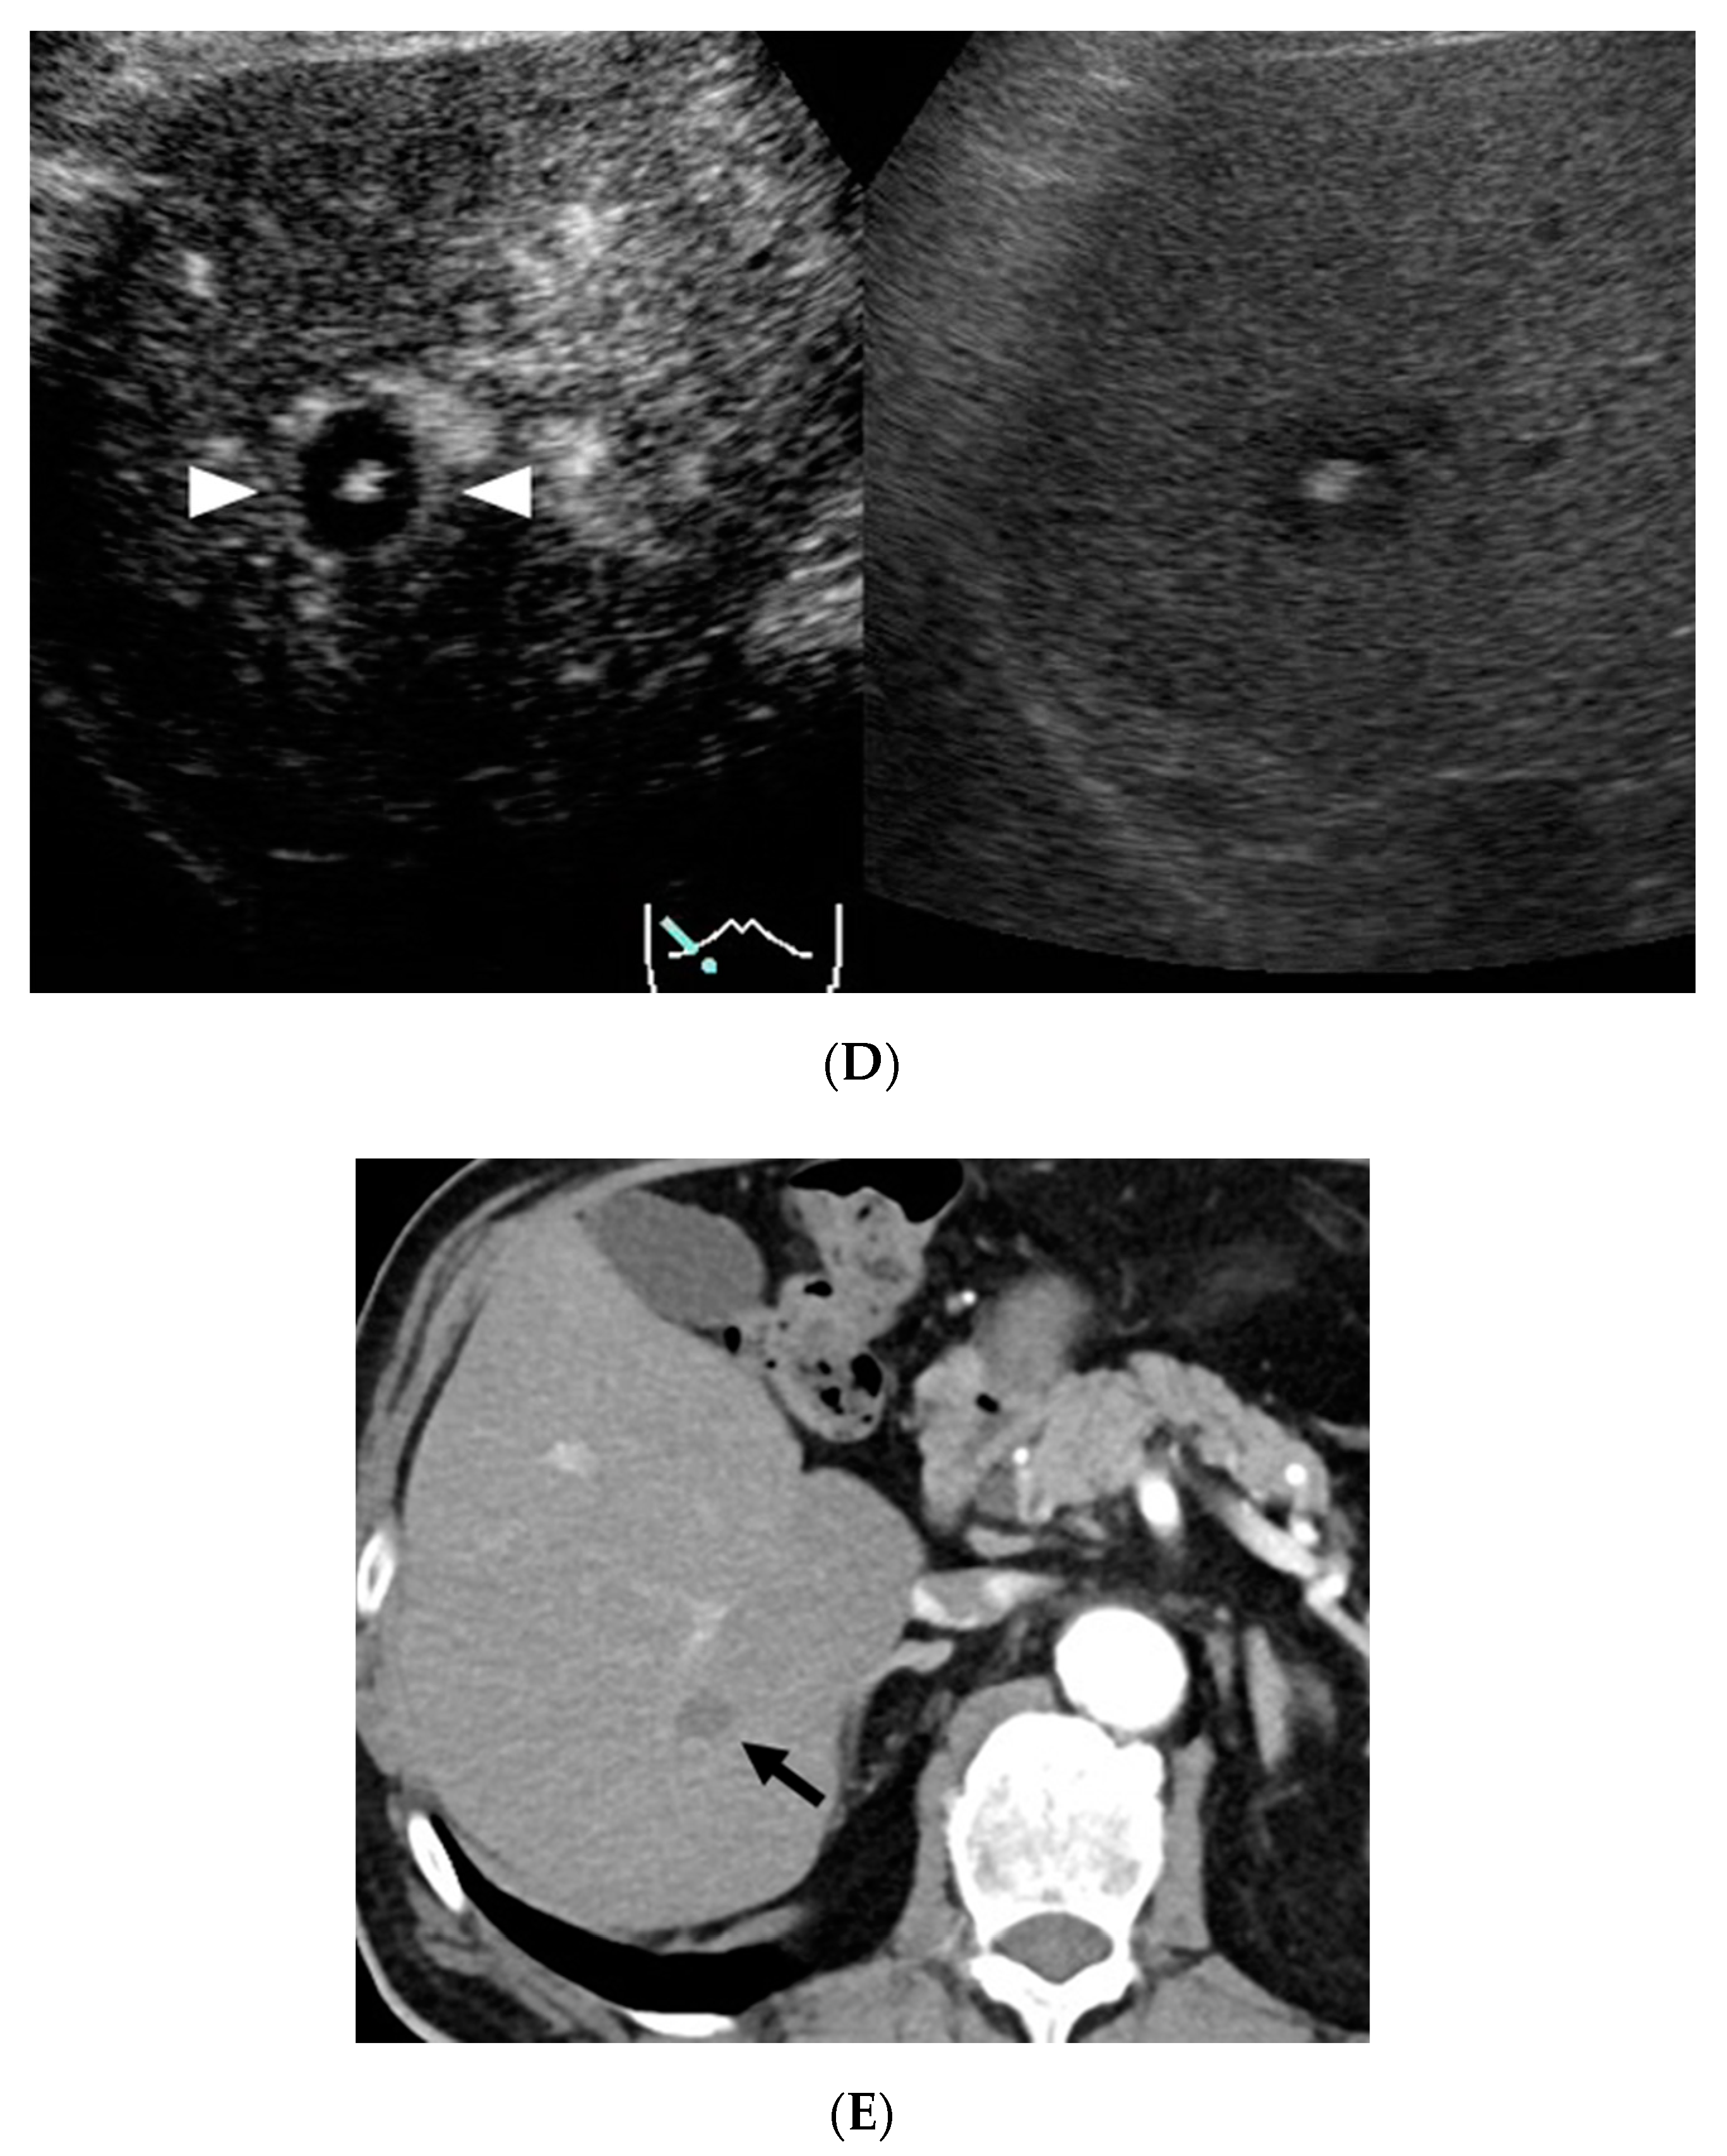

2.2. CEUS Imaging

2.3. CECT Imaging

2.5. Image Analysis